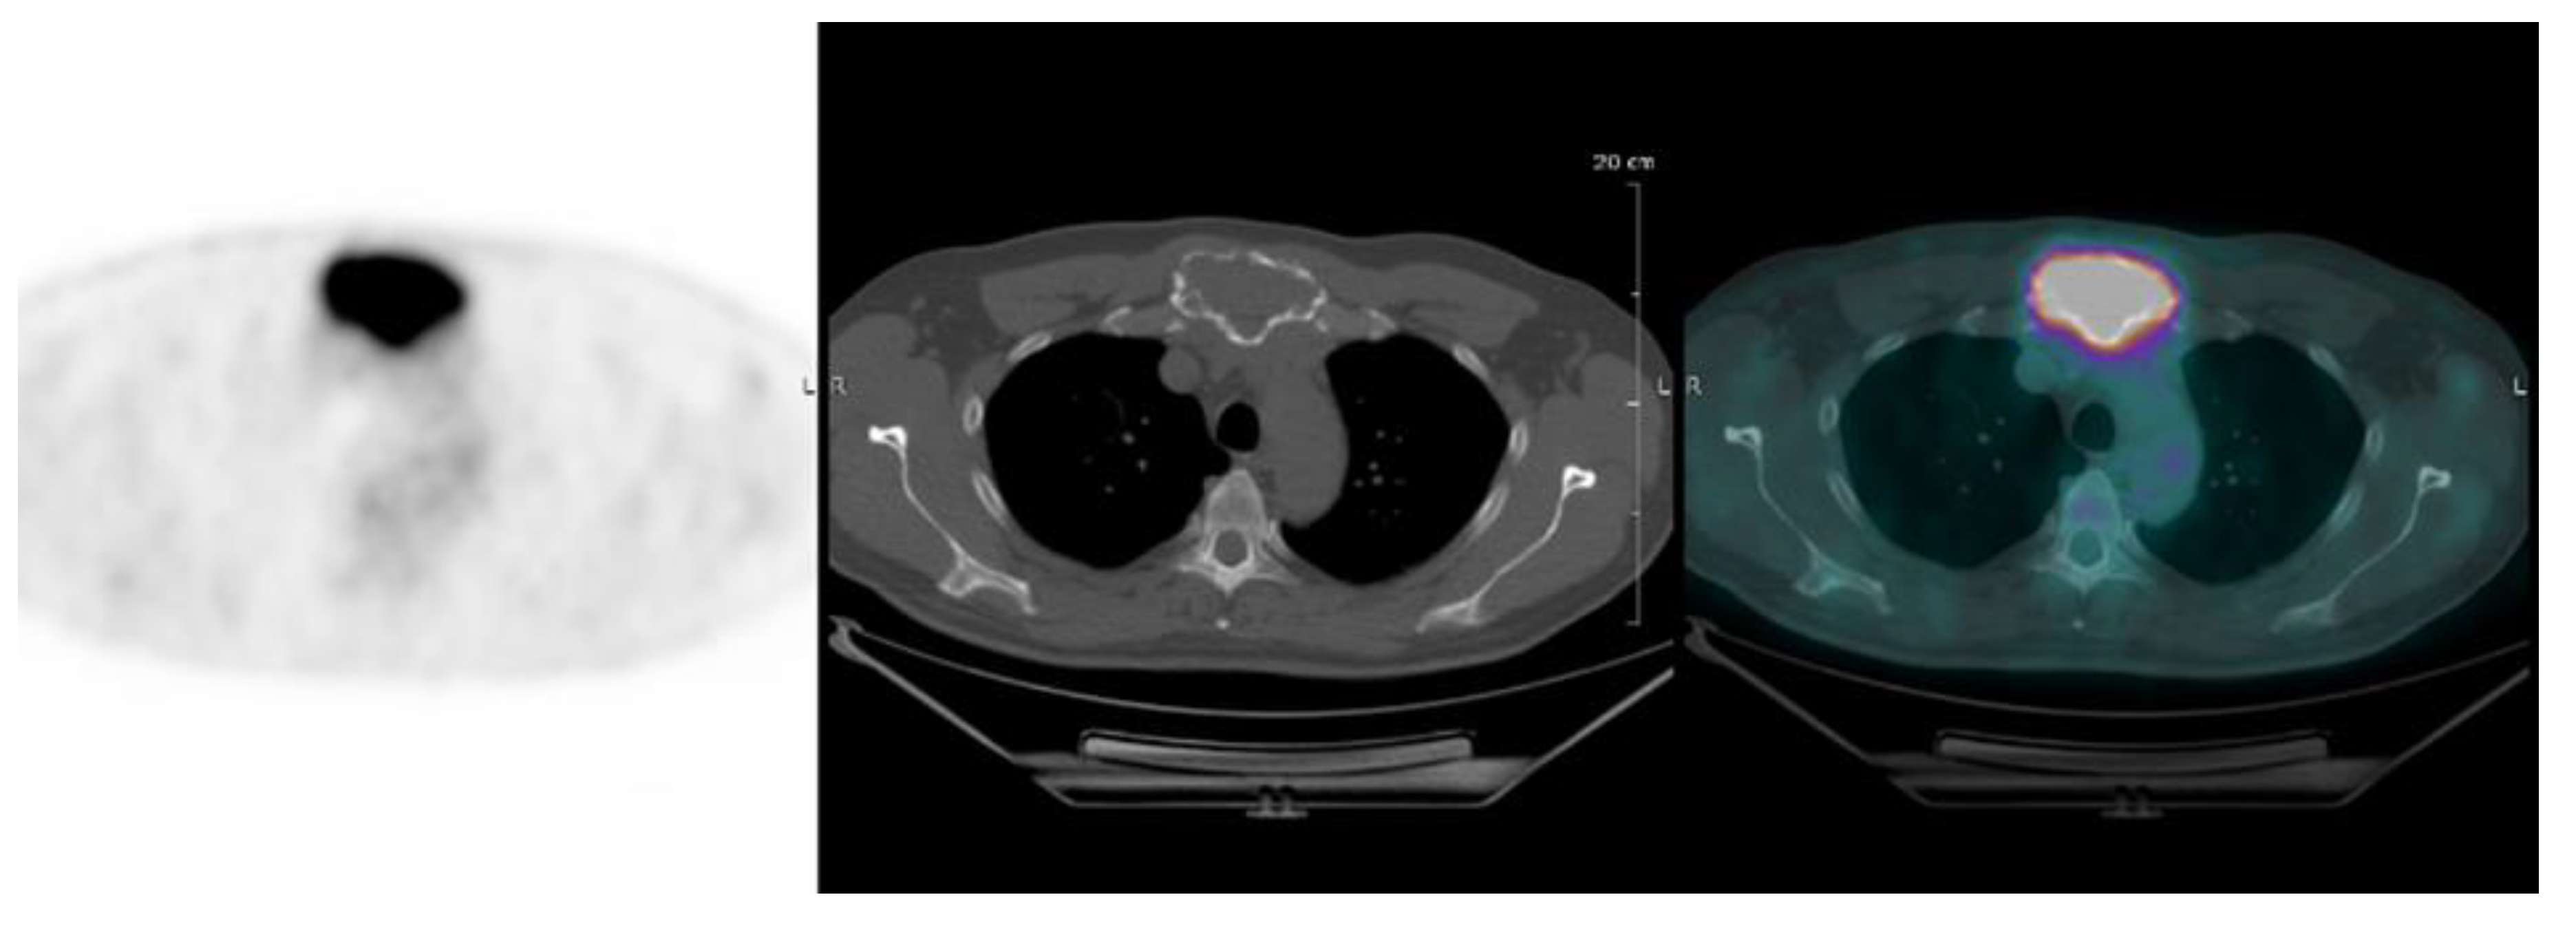

| Interpretation of PET Based on Prognostic Biomarkers | |||

|---|---|---|---|

| Lesions | Definition | Prognostic Biomarker | Reference |

| Focal lesion | Foci of uptake above the surrounding background noise on two successive sections with or without osteolysis on the CT image | Suggested as pejorative prognostic biomarker using cut off 3. | Bartel et al., 2009 [8] |

| Zamagni et al., 2011 [9] | |||

| Abe et al., 2019 [21] | |||

| EMD | Tissue invasion without contiguous bone involvement. | Presence of EMD suggested as pejorative prognostic biomarker | Zamagni et al., 2011 [9] |

| Moreau et al., 2017 [2] | |||

| Moreau et al., 2019 [19] | |||

| PMD | Soft tissue invasion with contiguous bone involvement. | Presence of PMD suggested as pejorative prognostic biomarker | Moreau et al., 2019 [19] |

| Diffuse medullary involvement | Homogenous diffuse uptake of the pelvic-spinal-peripheral skeleton higher than the liver background. | Prognostic value currently not demonstrated | |

| FL SUVmax | Maximal SUVmax of bone focal lesions | Suggested as pejorative prognostic biomarker using cut off of 4.2 | Zamagni et al., 2011 [9] |

| FDG-PET/CT abnormality | Presence of Focal lesion(s) and/or EMD lesion(s) and/or PMD lesion(s) and/or diffuse medullary involvement. | Absence of FDG-PET/CT abnormality considered as a favourable prognostic | Rasche et al., 2017 [16] |

| Abe et al., 2019 [17] | |||